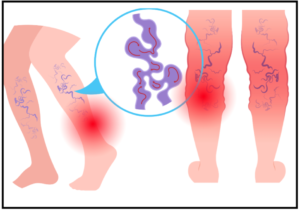

Read MoreVaricose vein Surgery

Varicose veins are a common vascular condition that could be...